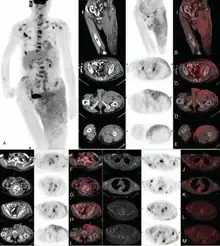

Extensive Invasive Extramammary Paget Disease Evaluated by F-18 FDG PET/CT

A Case Report |thumb|right|Due to the rarity of EMPD and lack of clinical knowledge, the disease is not very commonly diagnosed.[8] Patients are often misdiagnosed with eczema or dermatitis[8] and a delay of 2 years is expected from the onset of symptoms before a definitive diagnosis has been reached.[8]